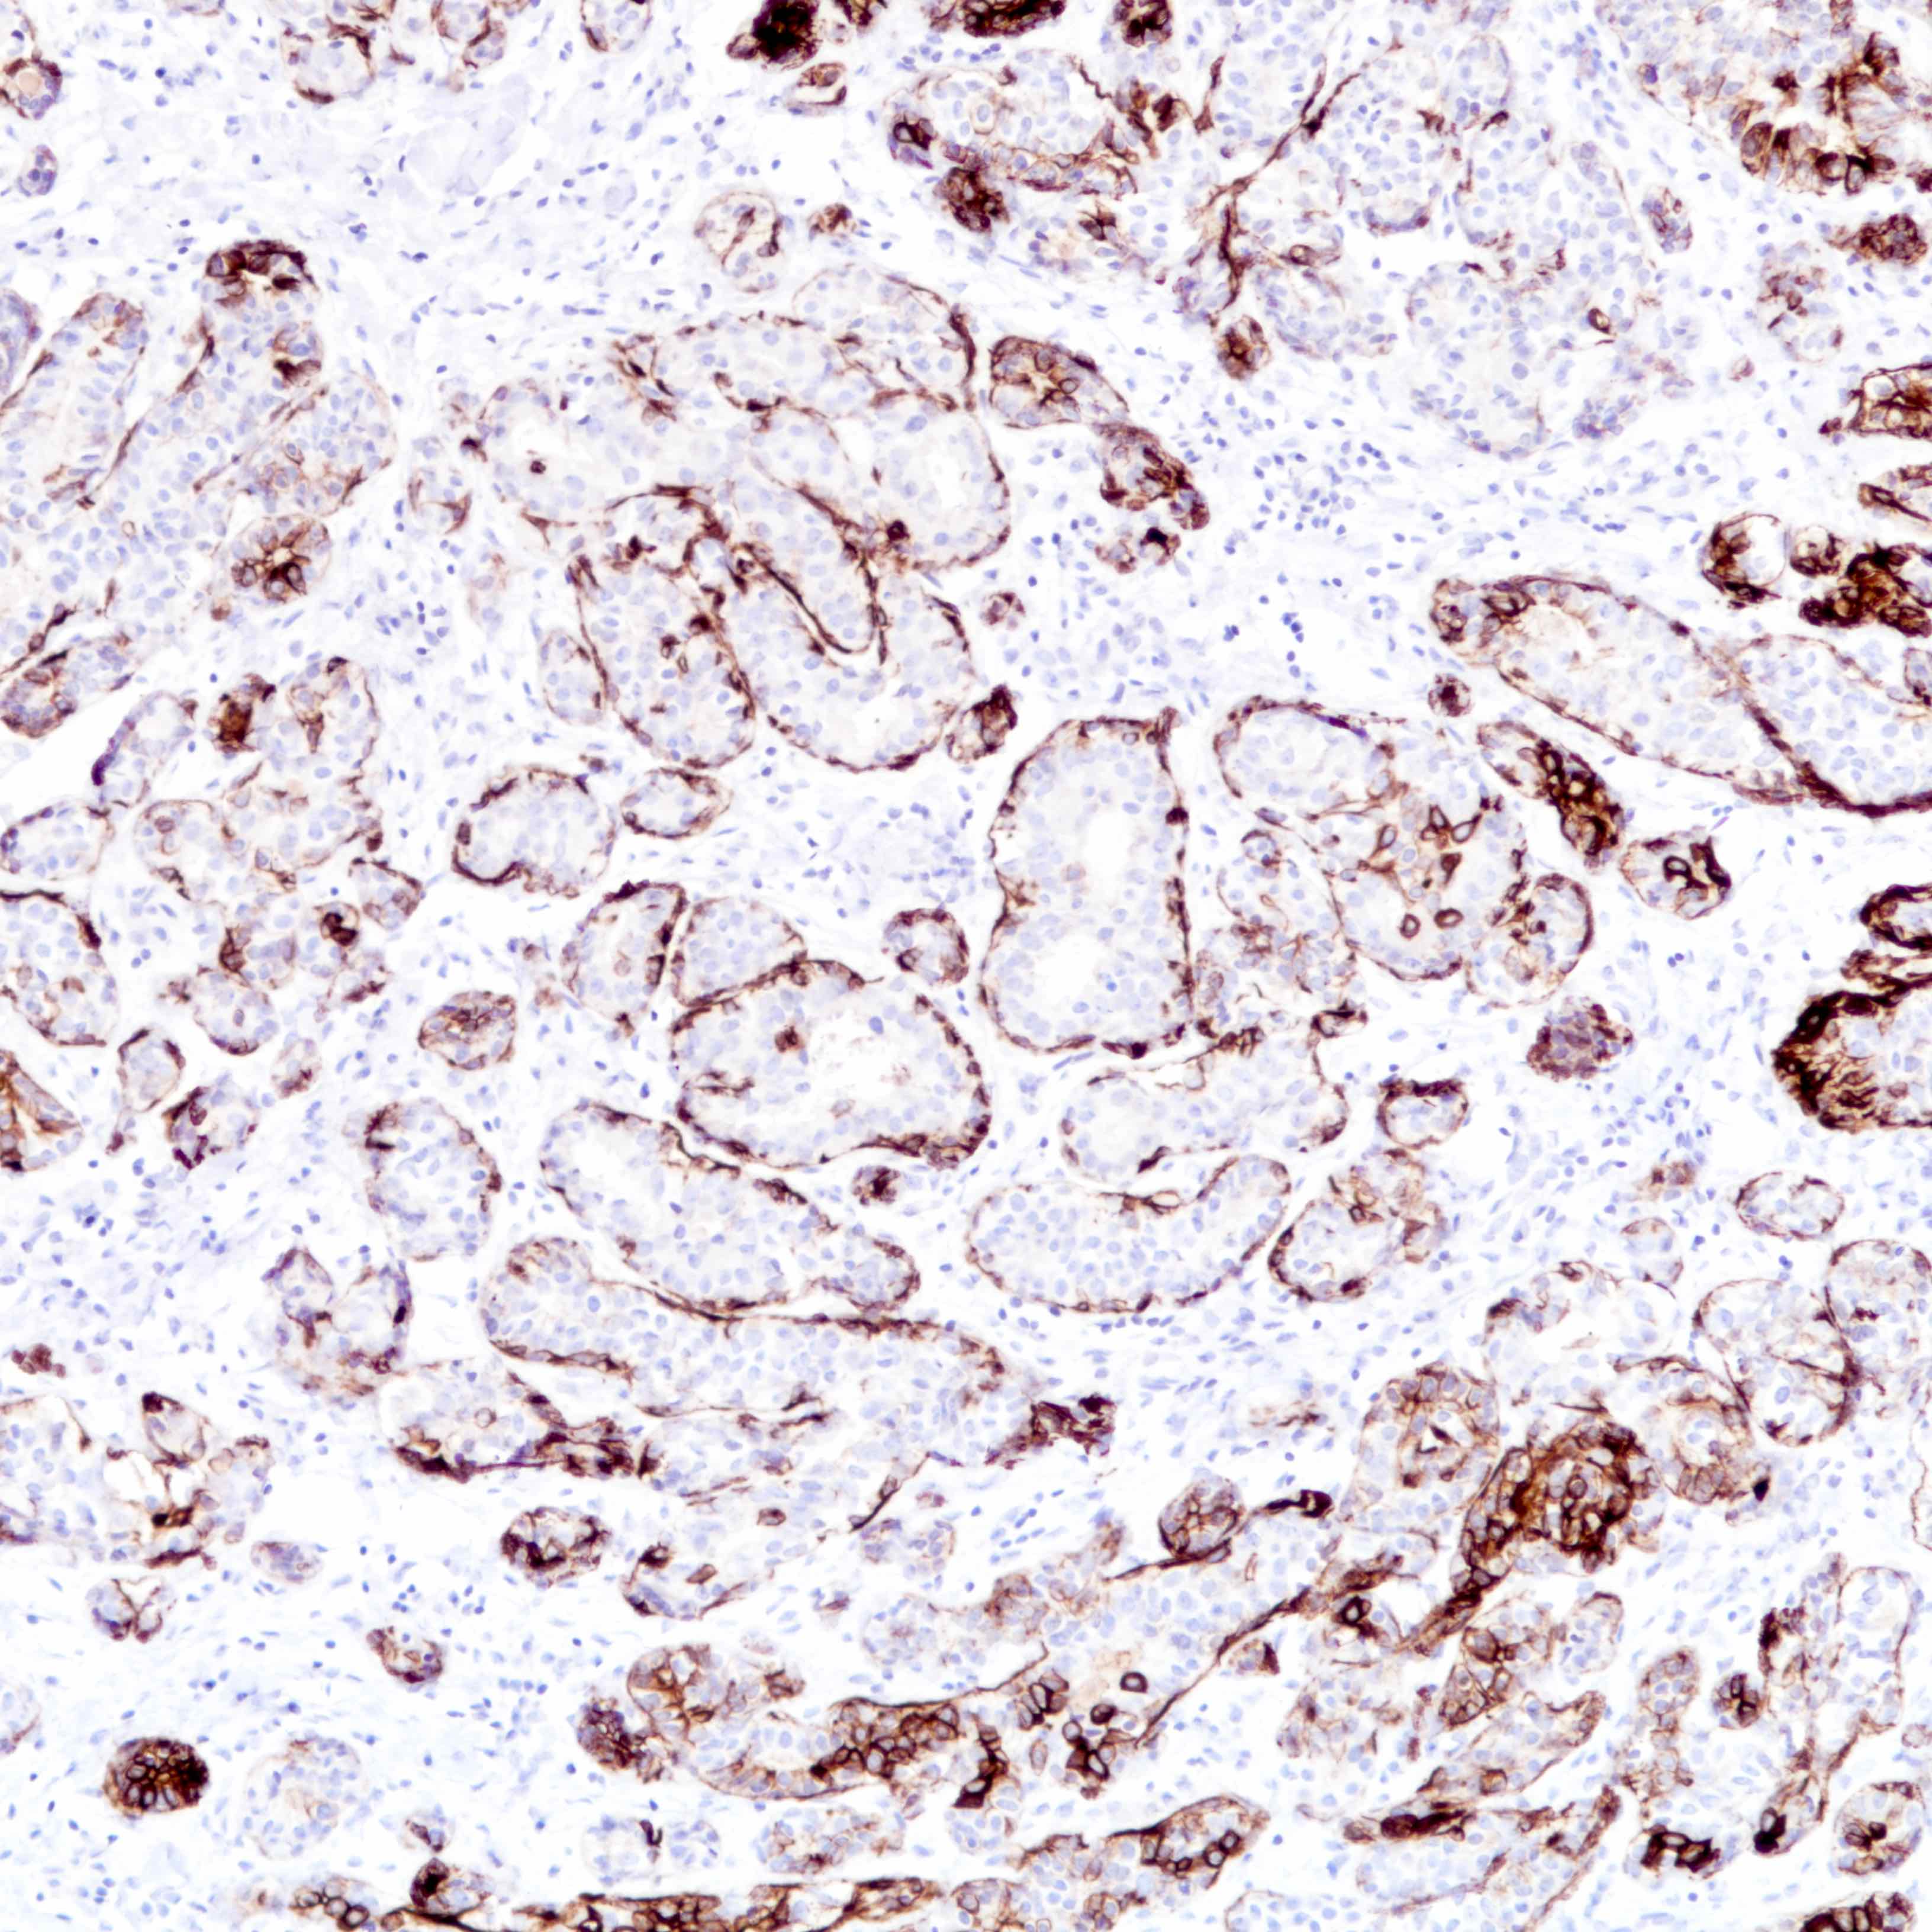

- Lined by an inner layer of luminal epithelial cells and an outer layer of myoepithelial cells

- Lined by an inner layer of luminal epithelial cells and an outer layer of myoepithelial cells

Microscopic (histologic) images

Contributed by Joshua J.X. Li, M.B.Ch.B. and Gary M. Tse, M.B.B.S.

Contributed by Jijgee Munkhdelger, M.D., Ph.D. and Andrey Bychkov, M.D., Ph.D.